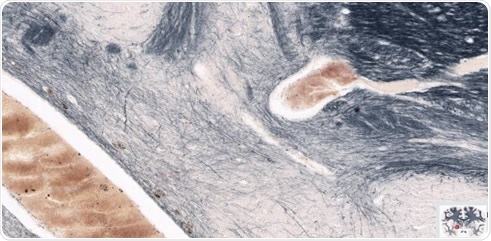

It is possible to use a tiling algorithm, so that for each brain slice, thousands of evenly spaced scans are captured at high resolution. The resolution achieved using the TissueScope, can reach up to 0.25μm at 40x magnification or resolution can be lower, at 0.50μm at 20x, or 1μm at 10x. This enables researchers to map the brain in detail, at a cellular level, and the potential to clarify uncertainties over observations made with lower resolution in-vivo imaging. Using suitable software, brain slice images can be compiled into a 3D volume. Hundreds of sections can be processed and viewed in just a few minutes, owing to the 3D histology software Huron offers that provides volumetric reconstruction of whole-mount slides. Furthermore, volumetric images from optical and confocal z-stacks can be read, visualized and investigated. Form there, scientists can proceed with cell counting, measuring the volume of specific regions and much more.

Figure 2. The brain in figure 1 magnified to highlight regions of interest in the left hemisphere. Image credit: Huron Digital Pathology.